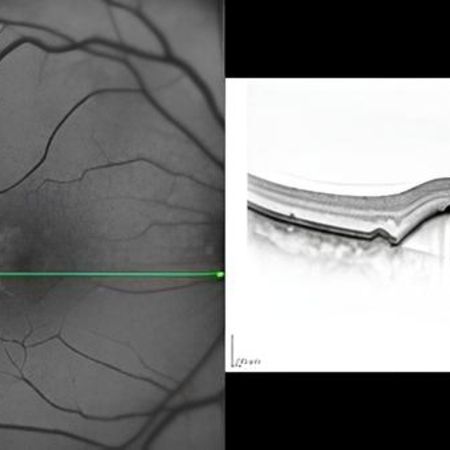

Optische Kohärenztomographie (OCT)

• Die tomographische Untersuchung, kurz OCT (Optische Kohärenztomographie) erstellt Querschnittsbilder der Netzhaut, des Sehnervs und der Hornhaut und ist eine wichtige Zusatzuntersuchung neben dem Spaltlampenmikroskop.

• Die Untersuchung ist nicht invasiv, ungefährlich, berührungslos und schmerzfrei.

• Mein Gerät nutzt die weltweit modernste Technologie und ermöglicht genaueste Diagnose über Erkrankungen der oben genannten Organe. Insbesondere für die Erkennung und Kontrolle der häufigen AMD (Altersabhängige Makula Degeneration), der Diabetischen Netzhauterkrankung und des Glaukoms (Grüner Star) ist die Optische Kohärenztomographie (OCT) von unschätzbarem Wert.

• Die OCT gehört heute zur Standarduntersuchung vieler Augenerkrankungen, die dann innerhalb kürzester Zeit diagnostiziert und dokumentiert werden können.